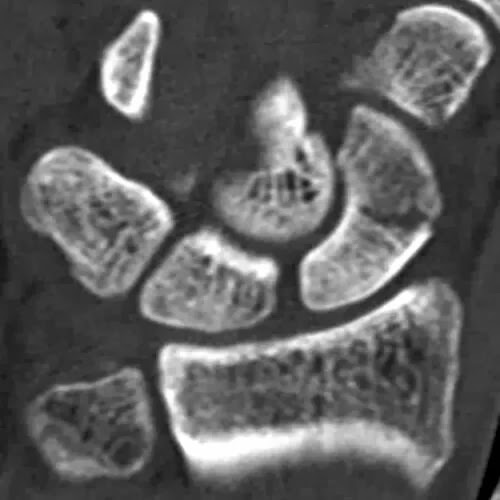

4º.- Tomografía Axial

También por TC se evalúan lesiones que no se recuperan y han producido necrosis avascular. Puedes consultar este caso clínico